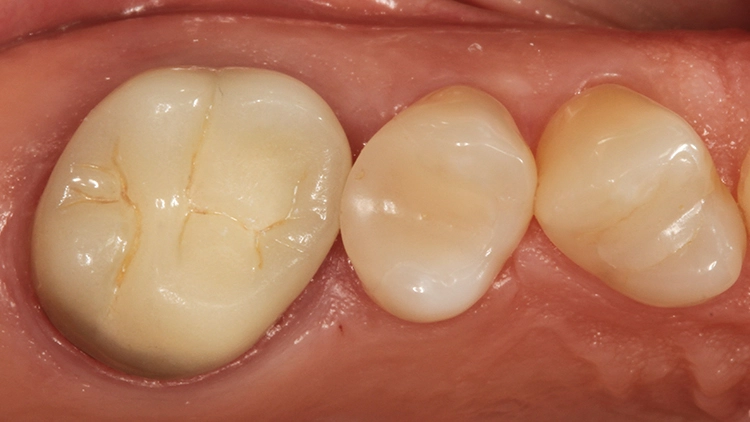

Der 55-jährige Patient störte sich an dem Randausbruch seines erst 10 Jahre alten Keramikinlays an Zahn 45 (Abb. 7). Er wünschte eine Neuversorgung mit Keramik. Nach eingehender Aufklärung und Beratung konnte er davon überzeugt werden, dass in der Dimension der Kavität eine direkte Kompositversorgung genauso funktionieren könnte.

Der sehr anspruchsvolle Patient haderte zunächst wegen der Ästhetik von „Kunststofffüllungen“: Er war der Überzeugung, dass hier keine adäquate Farbanpassung möglich sei, ließ sich aber auf den Vorschlag der direkten Kompositversorgung ein. Dieser Fall sollte dann eine Challenge für die Universalfarbe Venus Diamond One werden – aufgrund vorangegangener guter Erfahrungen von über 1,5 Jahren mit dem Material [10] konnte man sich ziemlich sicher sein, dass hier automatisch eine adäquate Farbanpassung stattfinden wird und gar keine hochspezifische individuelle Zahnfarbbestimmung erforderlich ist.

Die weitere Versorgung der Kavität erfolgte analog zu Fall 1 nach Anwendung eines klassischen Etch&Rinse-Mehrflaschenadhäsivs und schichtweiser Applikation und Polymerisation von Venus Diamond ONE (Kulzer) mit einem Hochleistungs-LED-Polymerisationsgerät > 1.000 mW/cm2 für jeweils 20 Sekunden Lediglich anstelle des Venus Diamond Flow Baseliners kam aufgrund der sehr hohen ästhetischen Ansprüche des Patienten Venus Diamond Flow in der Farbe A2 zum Einsatz – der Patient hätte keinen weiß-opaken Rand an seiner Restauration akzeptiert. Das Ergebnis (Abb. 9) überzeugte den Patienten nicht nur funktionell, sondern vorrangig ästhetisch: Auch hier passt sich die Universalfarbe perfekt an die Zahnhartsubstanz an. Zur Überprüfung der Ausdehnung der Überkappung wurde im Anschluss an die Versorgung eine Zahnfilm-Röntgenaufnahme erstellt (Abb. 10).